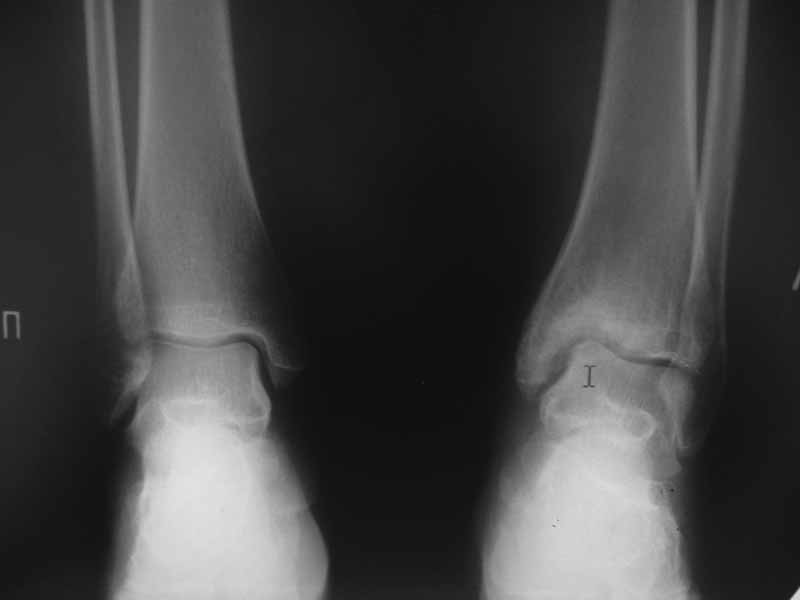

02.август.2010 г. - Травма получена в результате ДТП. Пациентка была доставлена в Городскую больницу №4. Диагноз при поступлении: закрытый оскольчатый внутрисуставной перелом лучевой кости левого предплечья в типичном месте со смещением; закрытый прелом обеих лодыжек левой голени со смещением и разрывом ДМС, полный вывих стопы; закрытый перелом наружного мыщелка большеберцовой кости левой голени без смещения. Была произведена репозиция отломков с наложением гипсовых повязок.

09.август.2010 г. - На контрольных рентгенограммах определялось смещение отломков лодыжек левой голени. Показана операция.

Диагноз на сегодняшний день на основании рентгенограмм, КТ (23.ноябрь.2011 г.), МРТ (06.сентябрь. 2011 г.): сросшийся перелом обеих лодыжек левой голени с формированием латерального подвывиха таранной кости. Неоартроз в суставе медиальной лодыжки с признаками асептического остеонекроза эпиметафиза большеберцовой кости и медиального суставного края таранной кости.